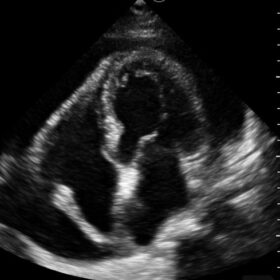

Mindray I3P WiFi Probe Image Gallery and Videos

Display mode: B, B/M, and Color, PW, PDI